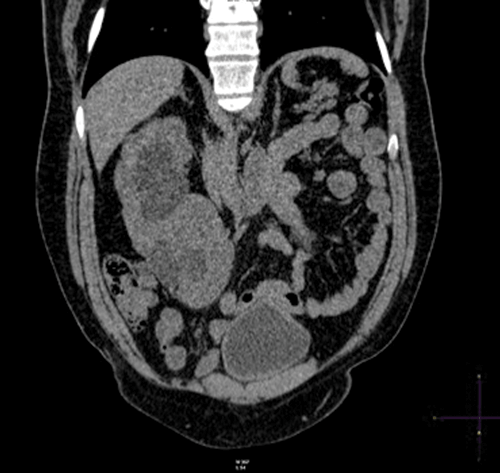

Plain coronal CT kidney, ureter, bladder (KUB) demonstrating crossed fusion renal ectopia; one case in 1000.

Theories include: a. abnormally situated umbilical artery preventing normal cephalic migration. b. the ureteric bud crosses to the opposite side inducing nephron formation in the contralateral metanephric blastema.

Left to right ectopy is more common (3:1).